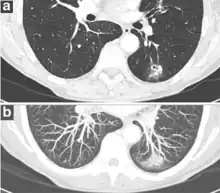

Lung nodule abutting a pulmonary cyst.[9]

• A lung nodule abutting a pulmonary cyst is a rare finding, yet indicating cancer.[9]